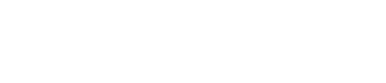

PRED:

Oslabené svaly močovej rúry

PO:

Posilnené svaly močovej rúry